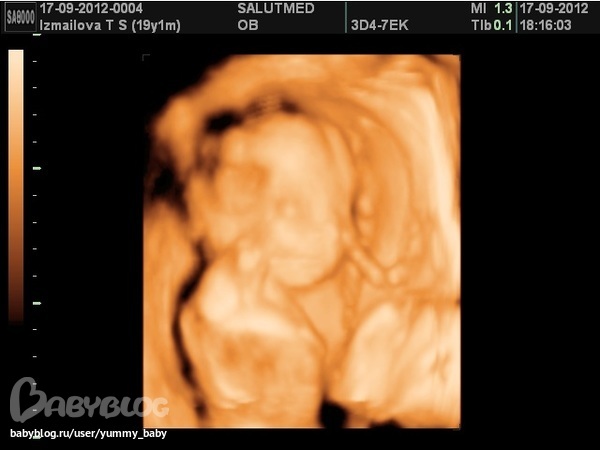

Результаты: УЗИ, КТГ, доплера, скринингаСходили мы сегодня к доктору и раскрыли тайну, у нас мальчик)) Роман Максимович.. улыбался нам, даже успели запечатлить улыбку. Я счастливаа)))